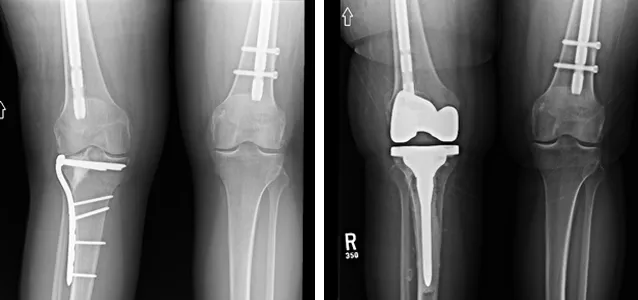

Figure 3: Intraoperative view showing a tibial plateau fracture before fixation.

Figure 4: Intraoperative image demonstrating reduction and provisional fixation with K-wires.

Figure 5: Post-fixation image illustrating plate and screw constructs used for stabilization.